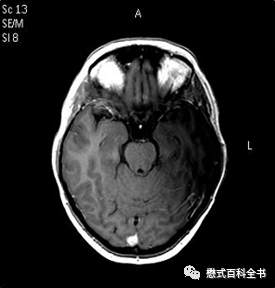

射频干扰伪影产生的原因是外界无线电信号干扰产生噪声,在图像重建的时候引入的伪影。一般通过查看原始的K空间数据或者图像表现就能发现。这种伪影表现非常典型,又叫拉链状伪影(Zipper Artefact)。

图8~9:拉链状伪影的表现

这种伪影的表现非常典型,可以说看过的可能一眼就识别了。理论上讲,前面讲的FID伪影也是一种射频干扰伪影,只不过比较轻微。

一般产生射频干扰伪影大部分情况是由于磁共振屏蔽没有做好,此时可以检查屏蔽门或者门是否关闭。另外有没有门对门的两台同样场强的磁共振对着安装设计,如果还没有解决必须请工程师来检测和调试。